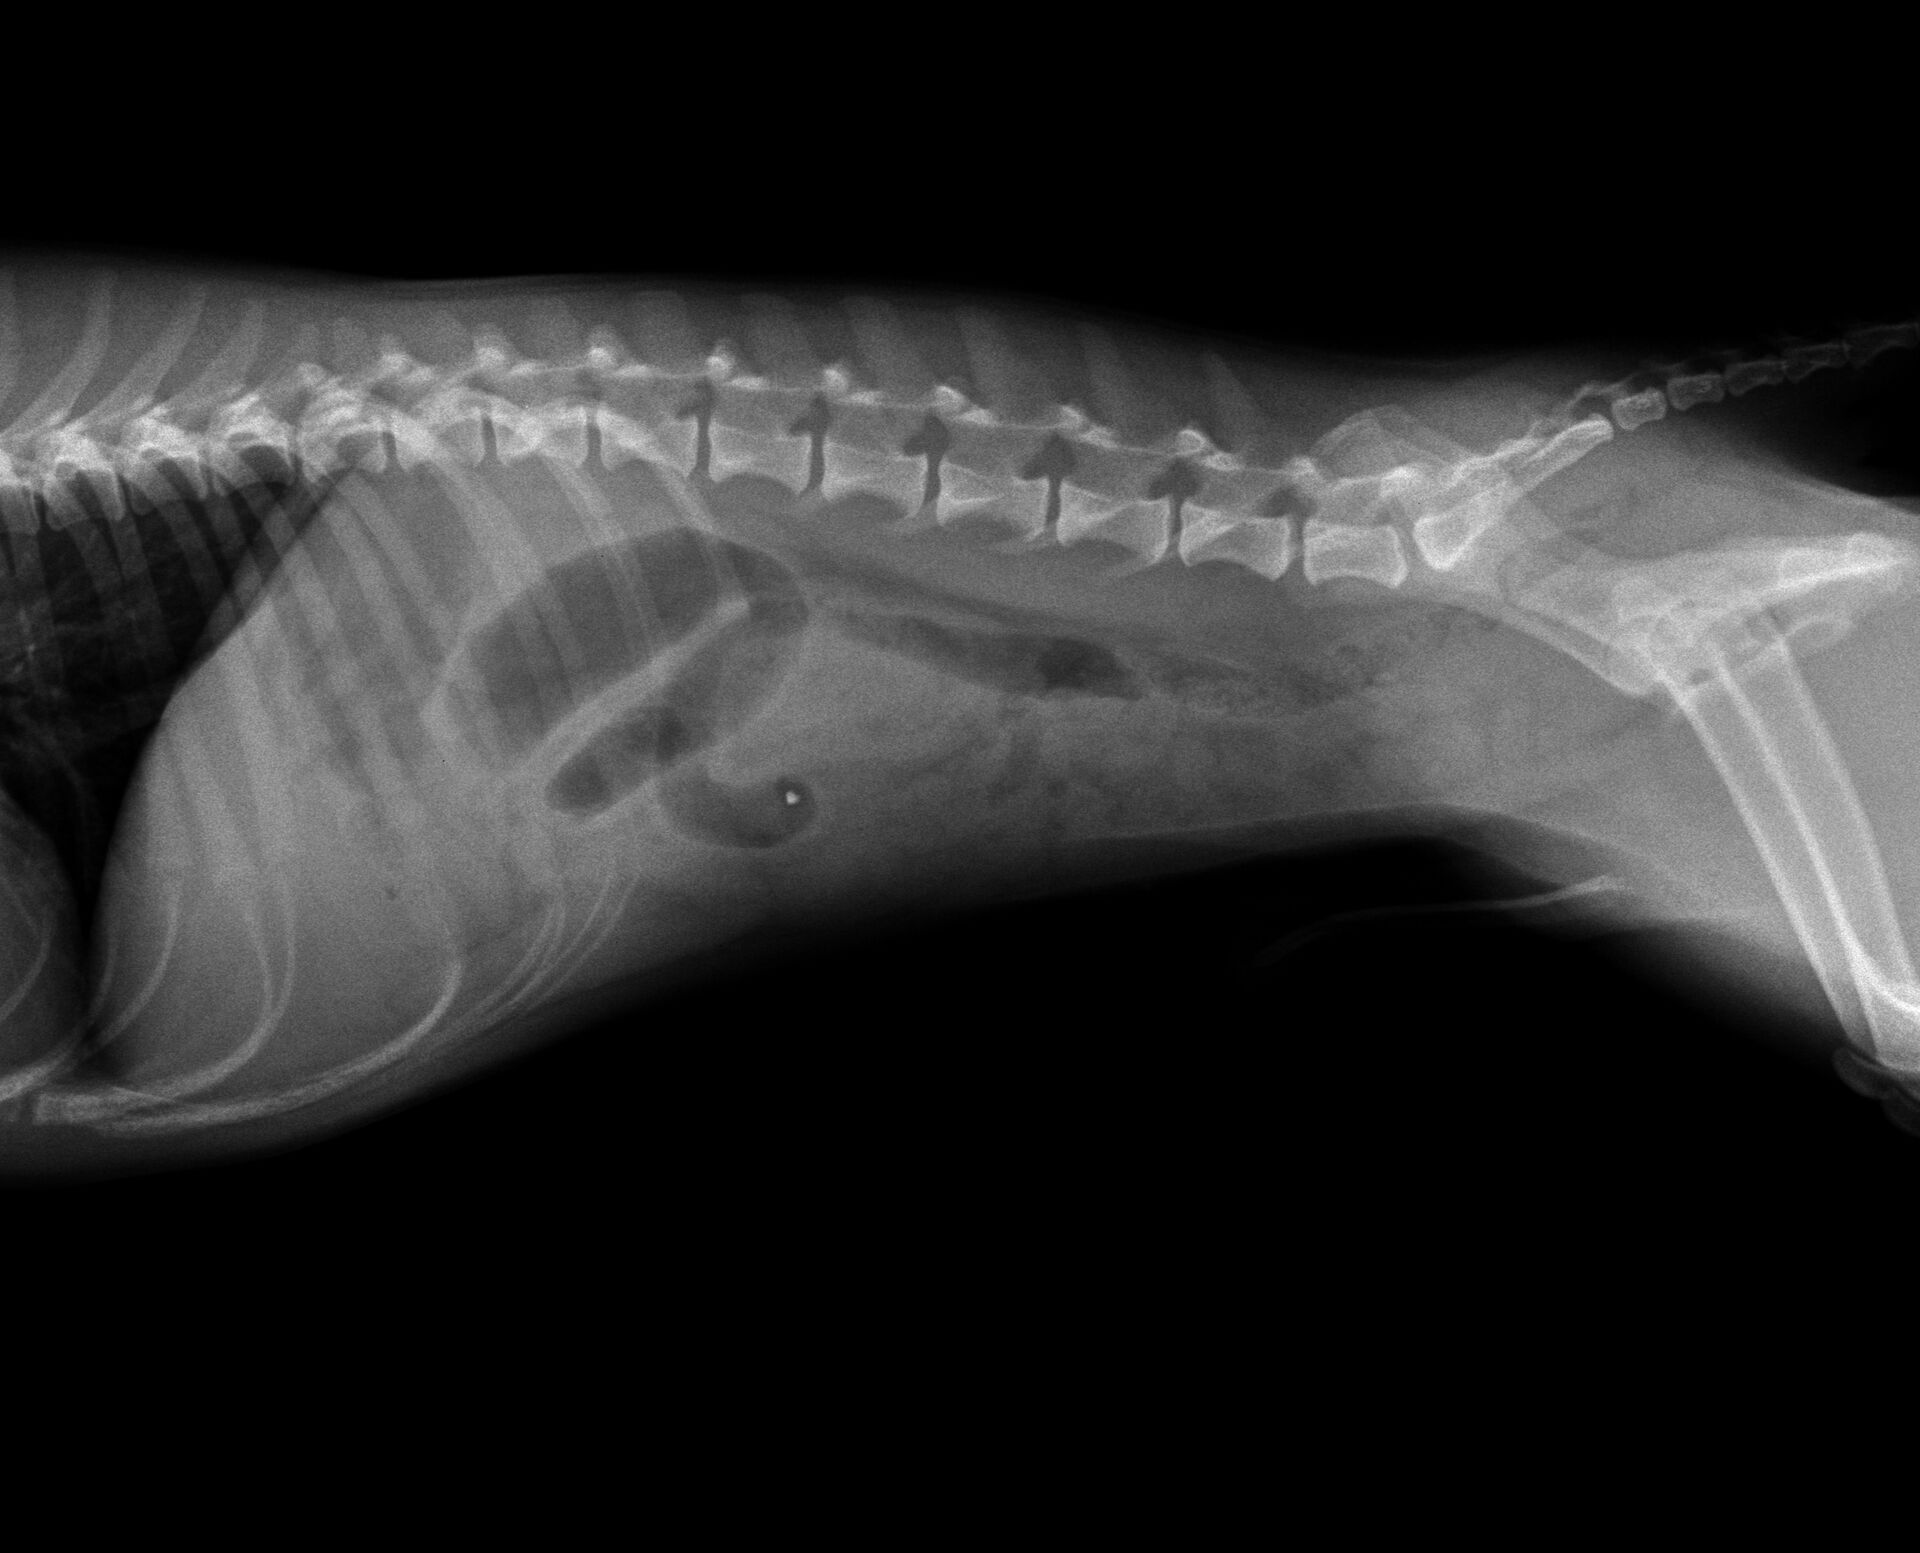

今年もあと1日となってしまいました。久々の投稿になってしまいましたが、今年最後の症例報告をさせていただきます。症例は1歳のジャックラッセルです。飼い主さんによると、日頃はすごく元気で食欲も旺盛なワンちゃんが突然何回も嘔吐し、食欲・元気がまったくなくなったとのことでした。元気で若いワンちゃんが突然、食欲廃絶、元気消失となると、一番疑われるのは異物の誤嚥です。そこで、すぐにレントゲンを撮りました。それが下の写真です。

胃から十二指腸にかけて普通より少しガスが多く認められました。益々異物による腸閉塞が疑われたので、バリウム検査を行うことにしました。その結果が以下です。